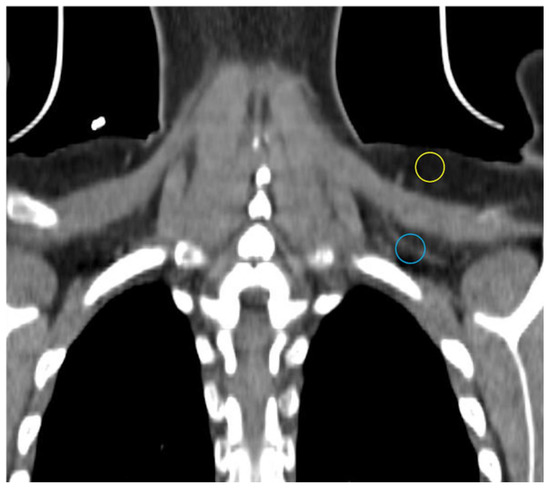

Computed tomography (CT) utilizes x-rays to generate a 3-dimensional dataset of tissue attenuation values that can be reconstructed into images in multiple planes. Different x-ray attenuation values of tissues form the basis of CT contrast. CT images have high resolution. iBAT is most often encountered in humans on CTs obtained during PET-CT studies in cancer patients. Although CT does not directly provide any functional data, radiodensity, which in the case of adipose tissue is largely determined by the ratio of fat to water, can be compared between different locations and quantitated using the Hounsfield scale [22,23,24]. The multilocular Ucp1-rich adipocytes have a higher fraction of water than their WAT counterparts and thus should be more radiodense [22,25]. Indeed, Prodhomme and colleagues found adipose tissue identified as metabolically active with FDG-PET has higher mean Hounsfield units (HU) than FDG non-avid WAT (−32.6 ± 26 vs. −99.6 ± 18.8 HU) [16]. HUs increase further with activation and utilization of lipid by BAT in rodents and humans [26,27,28]. Obese individuals have lower mean Hus in typical location of iBAT as in the supraclavicular region consistent with greater lipid content, and mean HU increases with weight loss [29]. In addition to supraclavicular depots, relatively high-attenuation fat depots in cervical, axillary, mediastinal, and intraabdominal locations may be iBAT [10,30,31]. CT demonstrates the known greater vascular density in BAT compared to WAT in our experience (Figure 2) [32].

Figure 2.

CT showing different density and vascularity of BAT versus WAT. Subcutaneous WAT with a darker appearance on conventional display and fewer vessels (yellow circle) compared with BAT (blue circle).